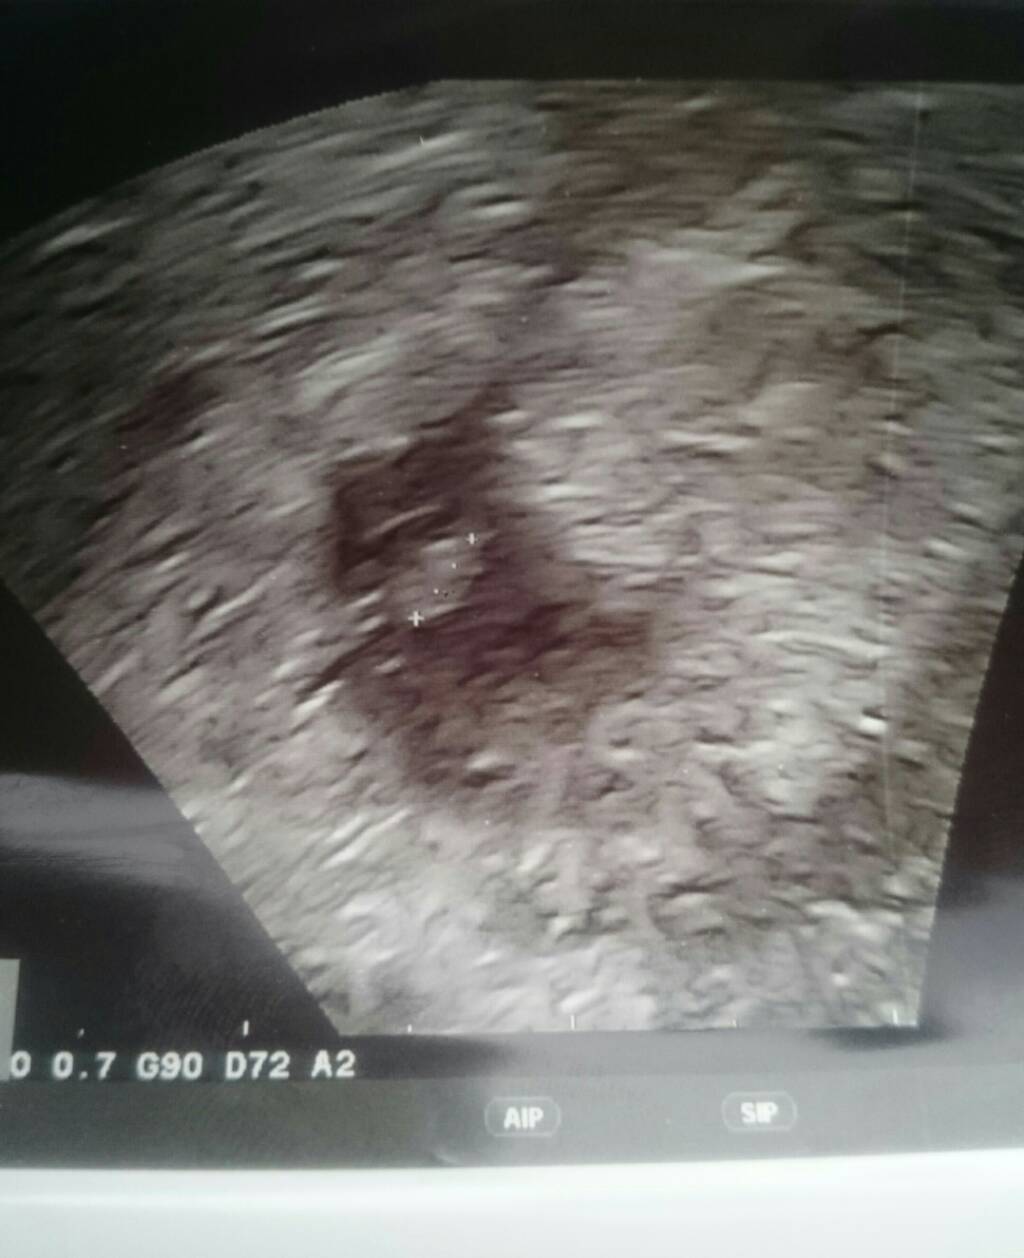

Eklerka ja zaraz walnę ta babe w kosmos normalnie!!Co to kur** za gadanie ze nie da nic na podtrzymanie!łaske Ci robi czy co?!ale sie zagotowalam!!!!!Popatrz jaki ja mialam pecherzyk i to bez zarodka w srodku!!Musisz brac progesteron,jego niski poziom bywa wlasnie powodem zapadnietego pecherzyka.Bralam 11 dni i jest teraz piekny okrąglutki a tez juz plakalam po wizycie!!Patrz jaki mialam jeszcze gorszy niz Twoj!!!